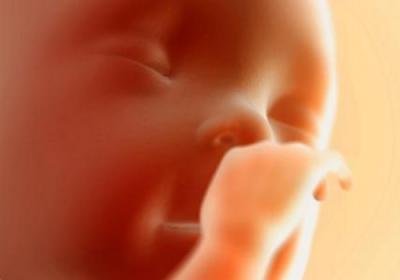

Одиннадцатая неделя беременности делает эмбрион плодом, он все больше становится похожим на человечка. Состояние беременной женщины в это время более или менее нормализуется. Но, все же, существует, кокая-то